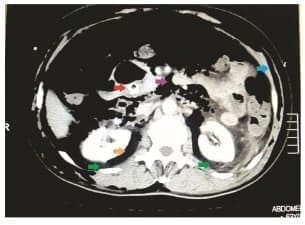

Durante la hospitalización, el paciente presentó signos de respuesta inflamatoria sistémica, por lo que se realizó una tomografía abdominal que mostró una colección retroperitoneal bilateral (figura 1), en relación con una fístula bilio-retroperitoneal, que fue confirmada endoscópicamente (figura 2).

Figura 1. Tomografía computarizada abdominal que muestra disección aérea masiva subcutánea

(flecha azul), neumoperitoneo (flecha morada), neumoretroperitoneo (flecha amarilla) y colección

retroperitoneal (flechas verdes). Se observa la prótesis plástica en la vía biliar (flecha roja).